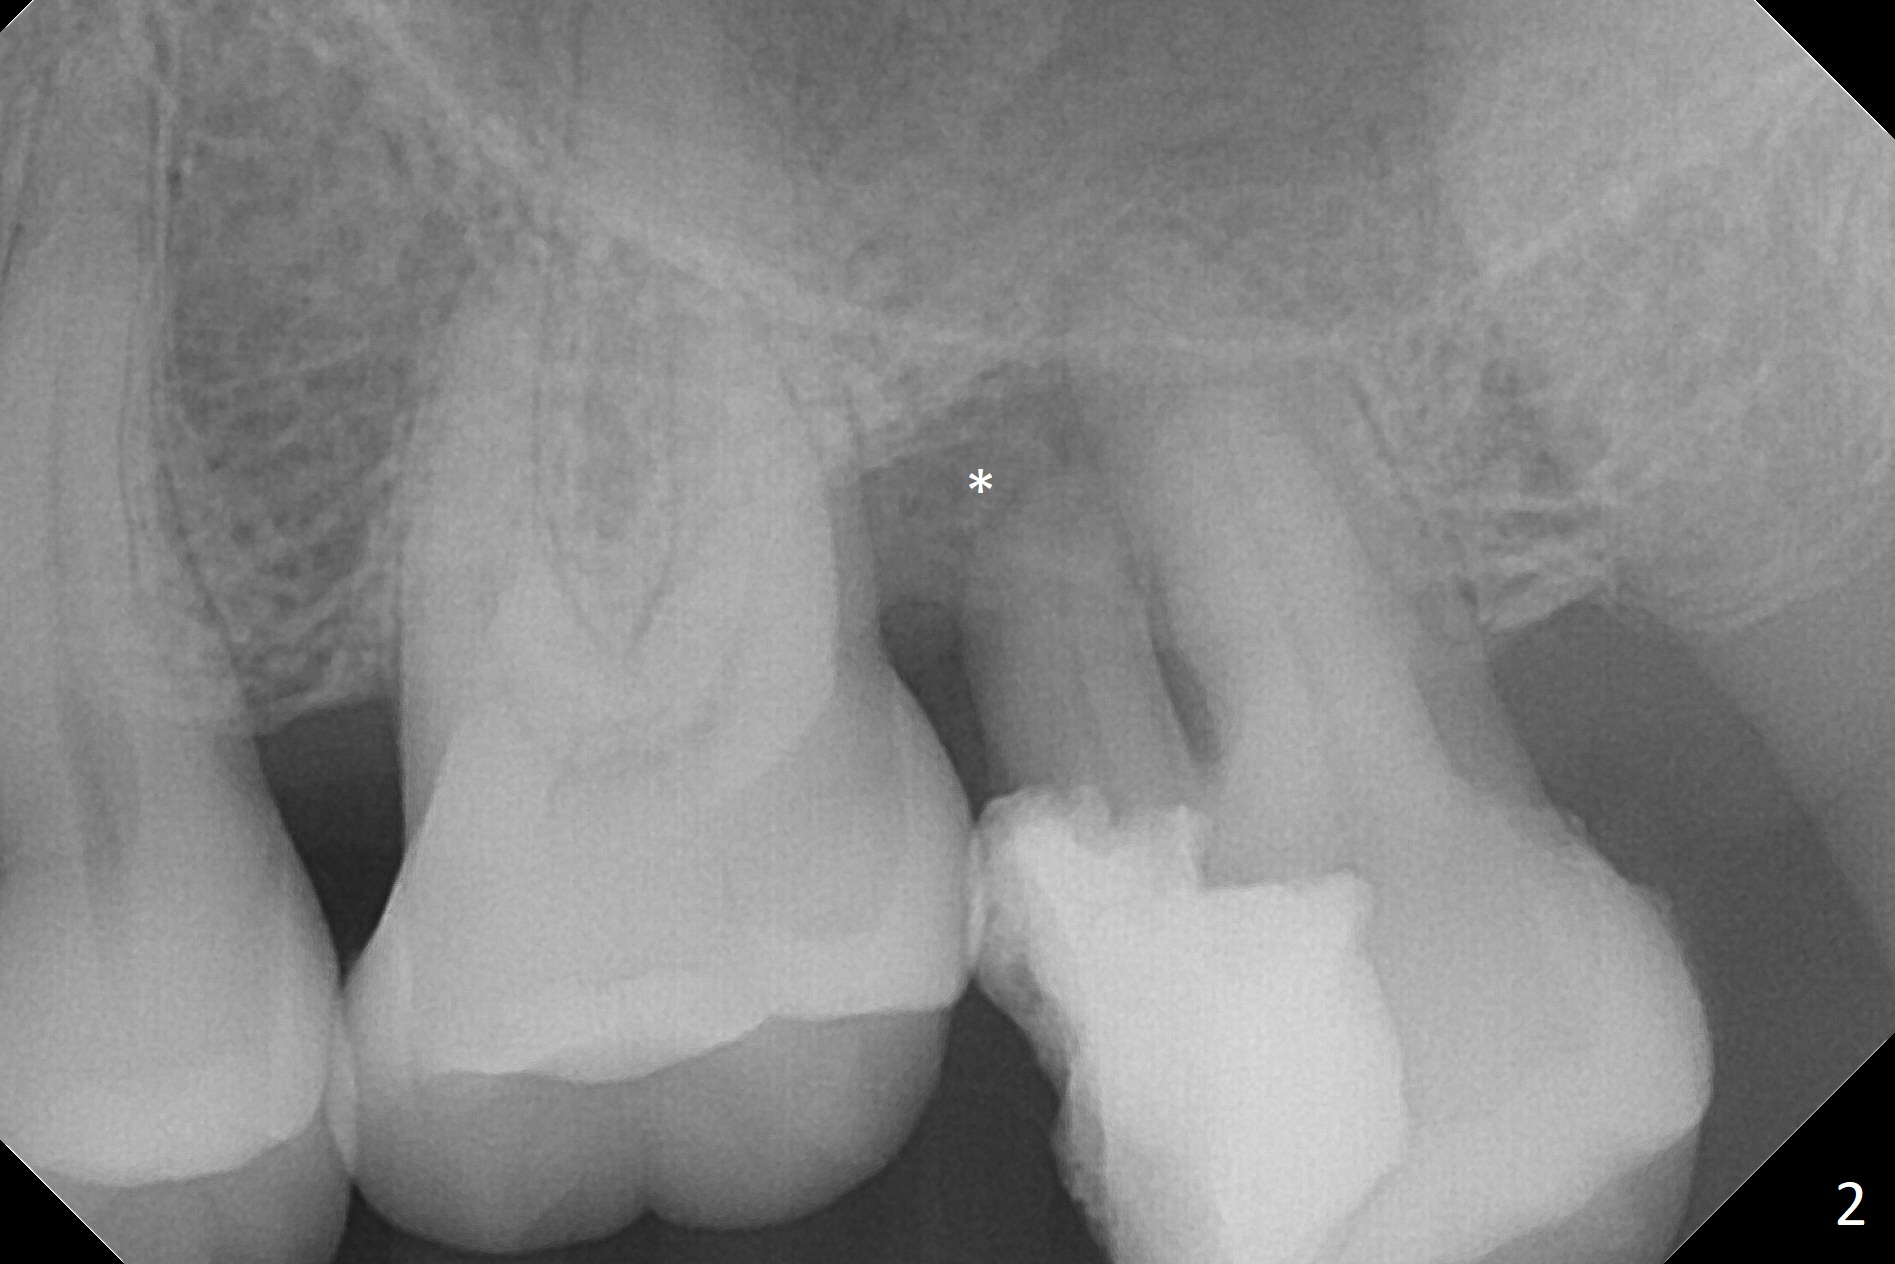

A 47-year-old man will return for #15 extraction and implant (Fig.1). Bone loss seems to be the most severe around the mesiobuccal root (Fig.2 *), from which the osteotomy should stay away (Fig.3). Take PVS impression for the sockets. Use Tatum osteotomes for sinus lift.